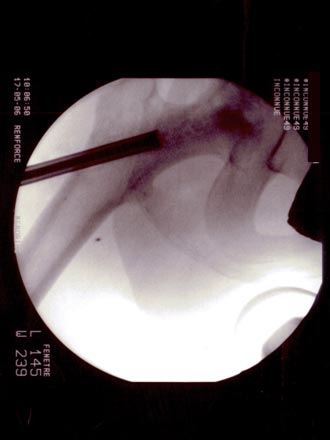

Technique opératoire Le trocart est introduit par voie pertrochantérienne et suit le trajet de la vis. Sa position dans la tête fémorale et dans la nécrose est repérée sous amplificateur de brillance de face et de profil. Une petite pince à séquestre retire les tissus fibreux et nécrosés circonférenciellement après repérage. Un lavage au sérum bétadiné complète le curetage. La moelle osseuse est prélevée (à l'aide du trocart de Mallarmé) sur la crète iliaque selon la technique classique. La moelle recueillie est d'autant plus riche en cellules souches qu'elle a été aspirée par petites fractions (2 ml). Ceci permet de réduire le degré de dilution par le sang périphérique. Elle est ensuite mélangée extemporanément avec le biomatériau. En général : 5 ml pour 5 cc de corail naturel. Sous contrôle Rx., le greffon est introduit à l'aide d'un trocart jusque dans la tête au niveau de la zone curetée : L'appui-contact avec 2 C.B est immédiat. Faut-il mettre en décharge avec traction et combien de temps ? Il ne sera possible de répondre à cette question que lorsque l'on saura avec précision la durée des phases de déminéralisation-reminéralisation du composite biomatériau-moelle osseuse aboutissant à de l'os néo- formé mécaniquement solide. C'est aux fondamentalistes de nous apporter la réponse.

OSTEONECROSE ASEPTIQUE de la H.D. Intervention en mai 2006